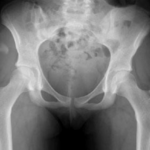

Le bilan d’imagerie comprend généralement :

- Des radiographies standards du bassin et des hanches,

- Une IRM ou une arthro-IRM pour analyser l’état du labrum et du cartilage,

- Un scanner ou arthroscanner dans certains cas afin d’obtenir une analyse morphologique fine et de planifier précisément la chirurgie.